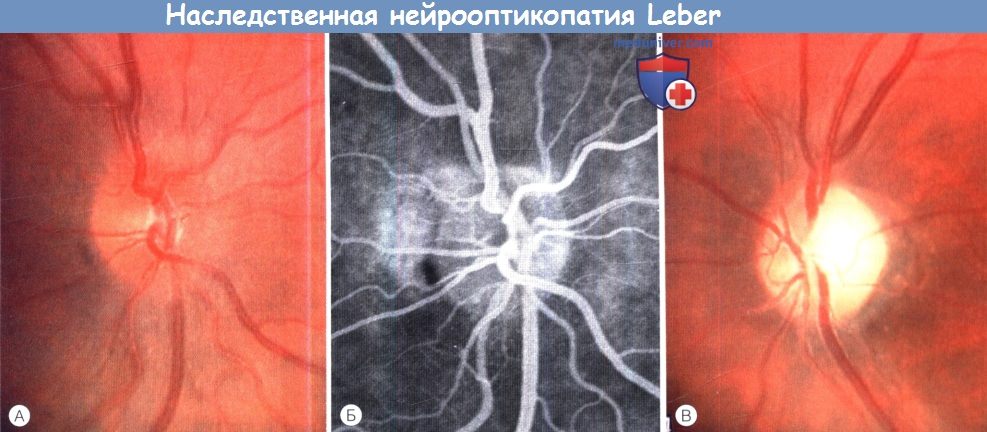

Атрофия зрительного нерва Лебера: Симптомы и лечение